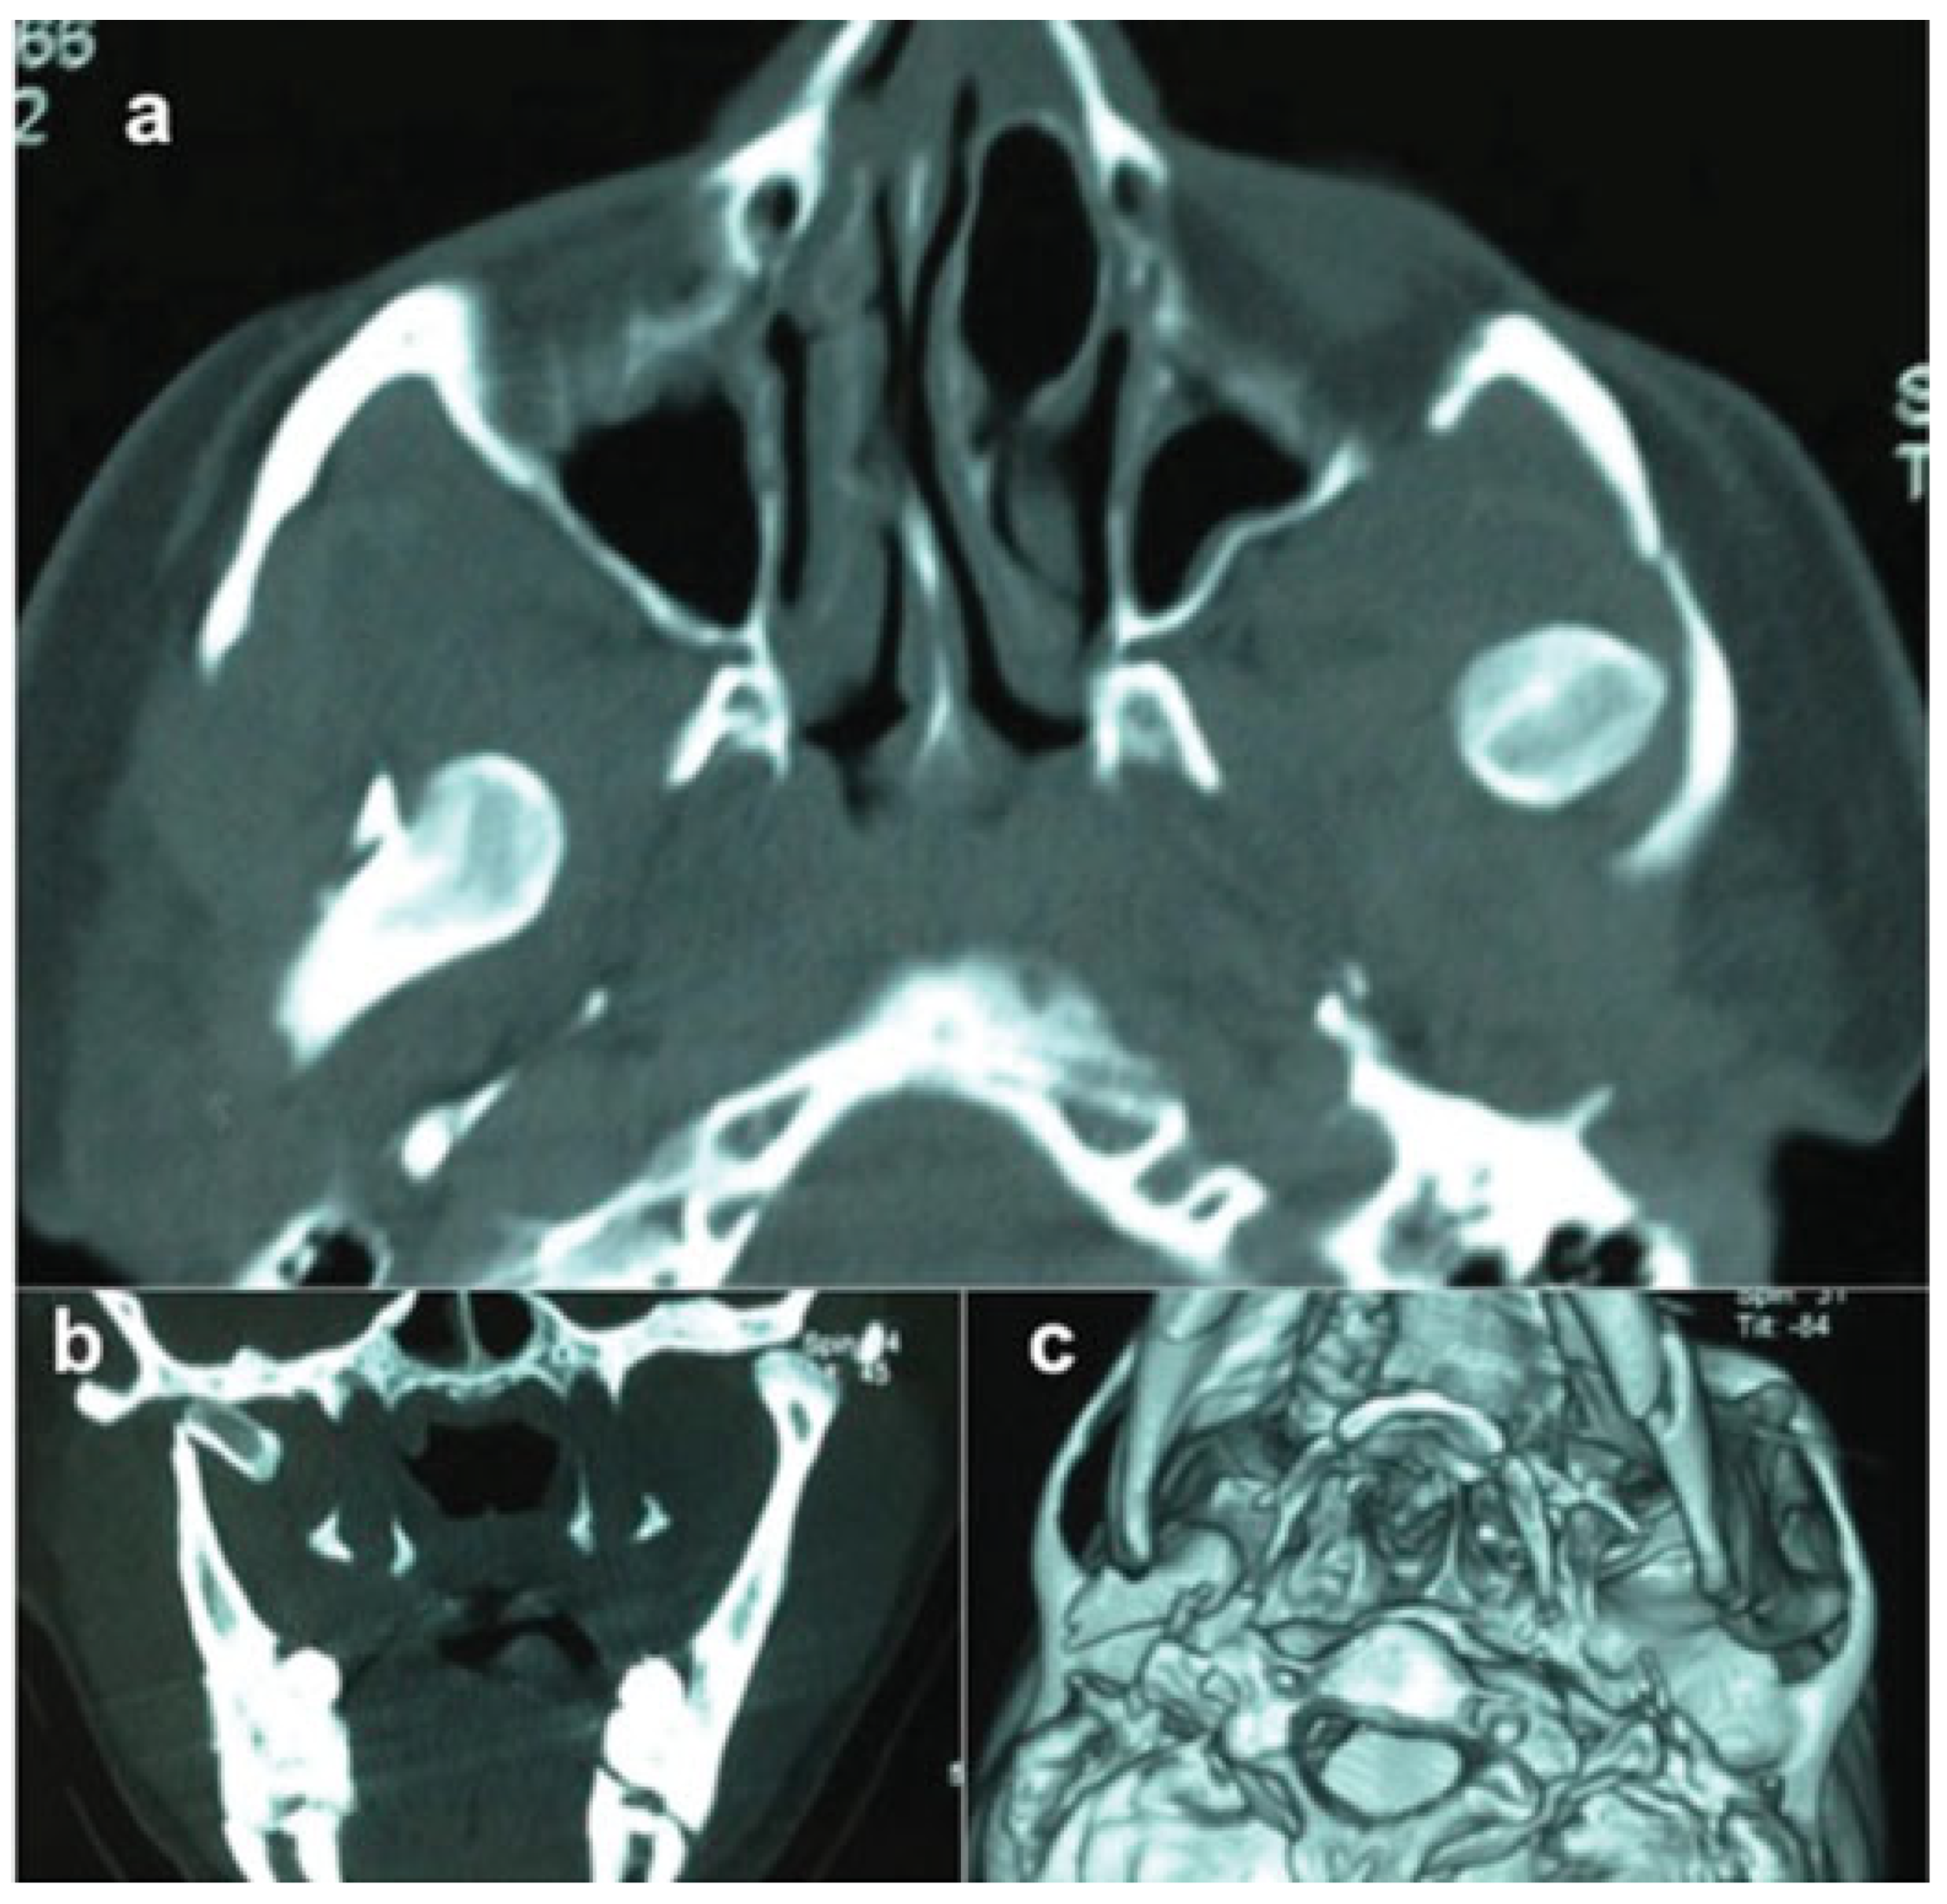

Traumatic Anterosuperior Dislocation of the Intact Mandibular Condyle into the Temporal Fossa

:Case Report